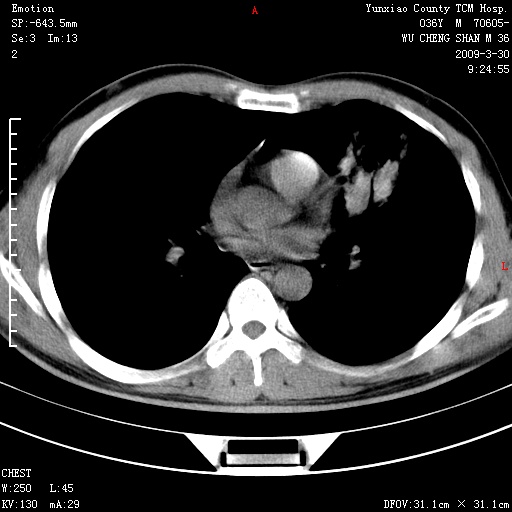

本院家属,胸痛,无咳嗽咳痰发烧病史,治疗一个月后病灶无明显改变,支气管镜示左肺慢性炎症,未见癌细胞,

胸痛,无咳嗽咳痰发烧病史,治疗一个月后病灶无明显改变,支气管镜示左肺慢性炎症,未见癌细胞,左肺下叶前段片状影,边缘不清,内见空支气管征,纵隔未见淋巴结肿大,周围无卫星灶,应考虑为炎性病变。

胸痛,无咳嗽咳痰发烧病史,治疗一个月后病灶无明显改变,支气管镜示左肺慢性炎症,未见癌细胞,左肺舌叶片状影,边缘不清,内见空支气管征,周围无卫星灶,应考虑为炎性病变。